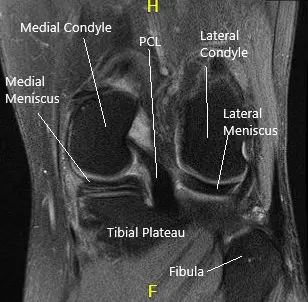

La resonancia magnética de la rodilla izquierda sugirió desgarro del cuerno posterior y de la unión del cuerno posterior/segmento del cuerpo en el menisco medial, con una leve extrusión meniscal hacia la canaleta medial y una condromalacia rotulana leve.

Resonancia magnética de rodilla en secciones sagital y coronal